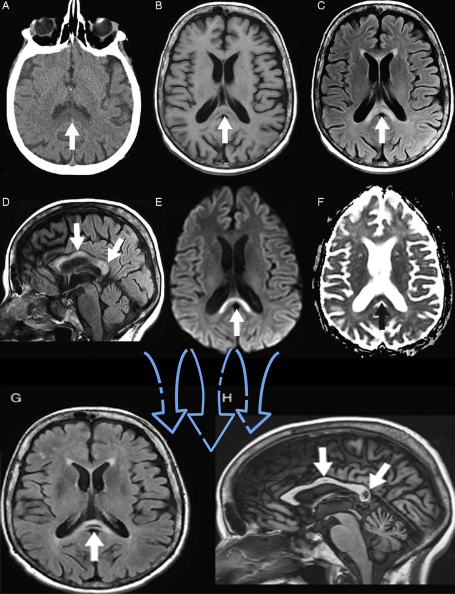

48岁,男性,长期饮酒过量20年,出现出现眩晕,胼胝体、侧脑室周围白质、内囊后肢对称性异常信号,扩散受限,诊断为原发性胼胝体变性急性期。

胼胝体压部病变及多发皮层对称性病变,表现为扩散受限

急性期原发性胼胝体变性(胼胝体压部及体部病变,CT呈低密度,T1WI呈稍低信号,FLAIR呈稍高信号,扩散受限)向慢性期转变,慢性期胼胝体压部病灶出现坏死或囊变,FLAIR呈低信号